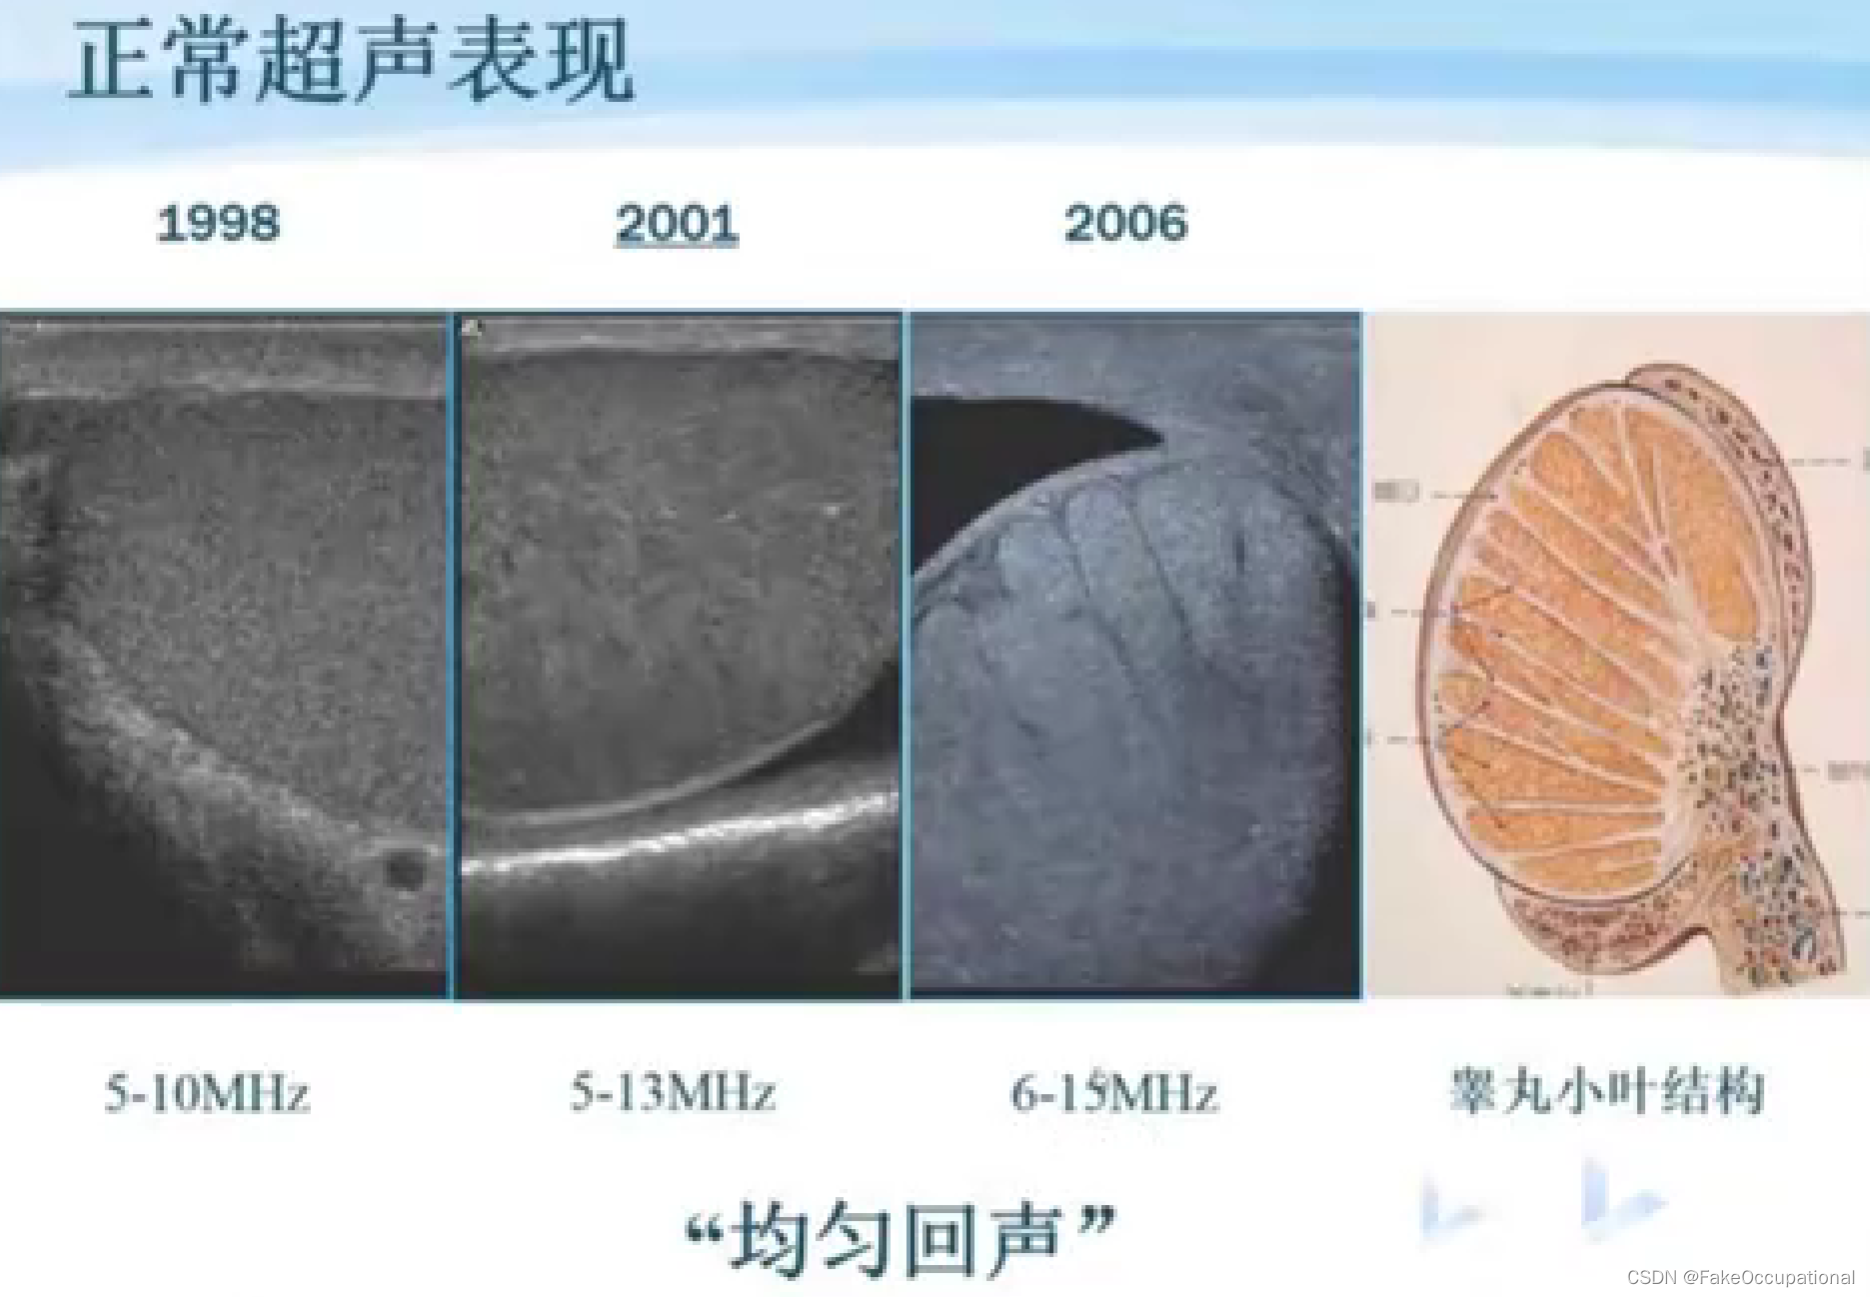

阴囊超声(和谐)